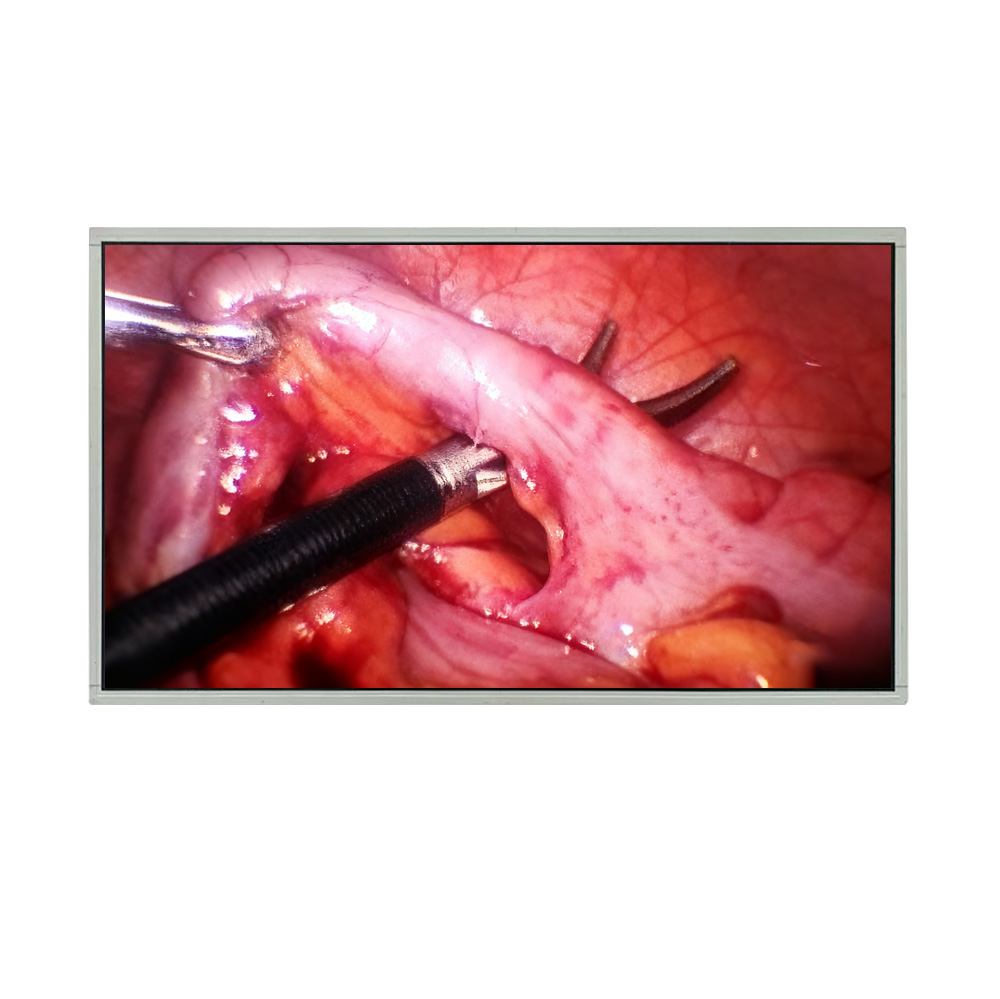

High Resolution Medical Display

How High-Resolution Medical Displays Improve Diagnostic Accuracy and Clinical Workflows

Explore how high-resolution medical displays enhance diagnostic accuracy, surgical visualization, and telemedicine workflows, delivering precise and reliable imaging for healthcare professionals.

Medical LCD Display: Key Requirements, Applications, and Technology Trends

An overview of medical LCD displays, covering technical requirements, healthcare applications, and key factors that influence display performance in modern medical environments.